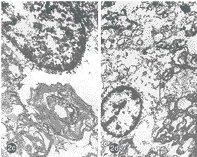

图1a 5min对照组(A组):灰质小片状出血(HE×462) 图1b 5min 654-2实验组(B组):灰质小片状出血较对照组轻(HE×462) 图1c 10min对照组(C组):神经元固缩、溶解,大片出血灶(HE×200) 图1d 10min 654-2实验组(D组):白质内大片出血灶(HE×200) 图2a A组:线粒体、内质网肿胀,髓鞘板层轻度分离(×10000) 图2b B组:线粒体肿胀,内质网扩张,神经纤维轻微水肿(×10000) 图2c C组:神经元重度肿胀,大部分线粒体及内质网消失,核膜及胞膜结构不清,核固缩(×10000) 图2d D组:神经元重度肿胀,部分线粒体、内质网破裂,神经纤维水肿(×9000) 图3a A组:微血管不同程度环状狭窄,粗细不均,充盈差(×100) 图3b B组:微血管走行自然,无明显狭窄(×600) 图3c C组:微血管密度低,破裂出血(×200) 图3d D组:微血管密度较低,粗细不均,亦可见破裂(×600)

2.4.2 透射电镜 A组神经元及神经纤维间隙增宽,髓鞘有分层及松解。内质网扩张(图2a,插Ⅳ);B组神经元及神经纤维间隙增宽不明显,神经元线粒体形态基本正常(图2b,插Ⅳ)。C组核固缩,血管内皮细胞基底膜破裂(图2c,插Ⅳ);D组亚细胞结构改变较C组轻(图2d,插Ⅳ)。